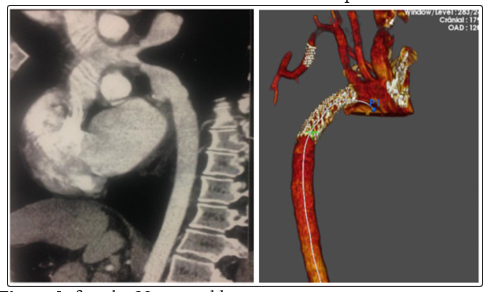

In our study we had associations of aortic aneurysm and stenosis of subclavian arteries (fig.1), multiple localizations of arterial stenosis (fig.2), as well as aortic stenosis associated with renal artery stenosis in 8 case (fig.3)

Figure 3: female, 23 years old, Hypertension under tritherapy + claudication of the right upper limb.

Lesion: aortic coarctation + tight stenosis of the sub clavian post vertebral artery.

Procedure: Thoracic endoprosthesis + TLA -Stent of sub clavian artery

Evolution: good, improvement of the blood pressure under monotherapy with a good right radial pulse.